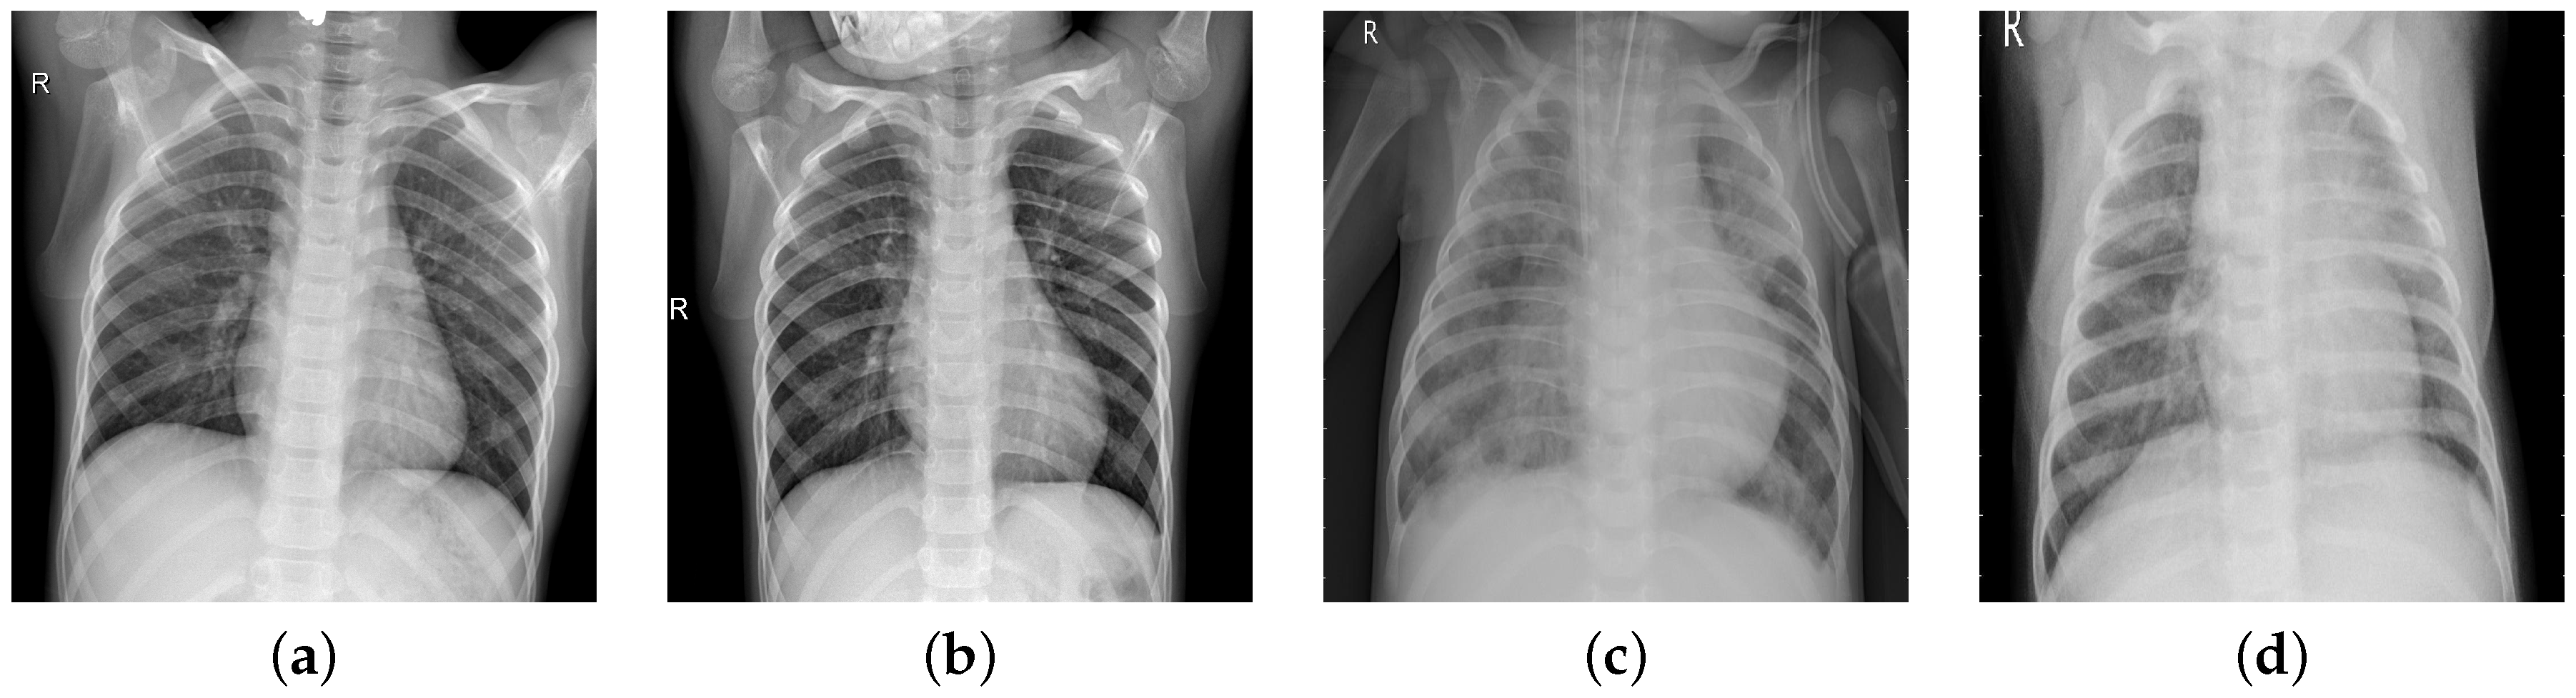

In chest radiographs radiographic features of a normal person include clear dark lung fields, well-defined lung borders, clear vascular markings, and a midline trachea. The chest radiograph of a person infected with pneumonia will exhibit localized or diffuse opacities, caused by fluid or pus-filled alveolar spaces. In Figure 1, we can observe the differences in the two types of images.

Figure 1. Normal images (a,b); pneumonia images (c,d).